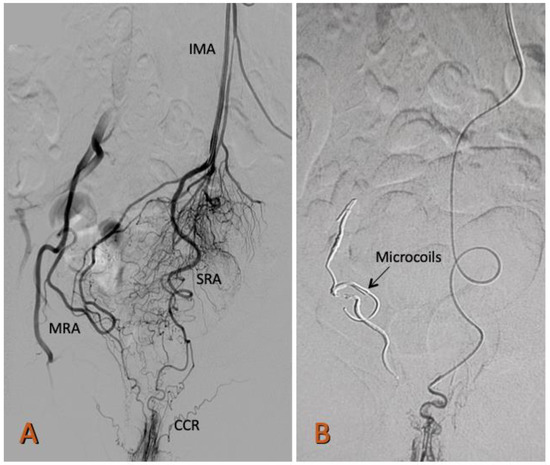

Using a 0.035-inch, 150 cm hydrophilic guidewire (Radiofocus, Terumo, Tokyo, Japan) and a 5F, 125 cm MPA catheter (Cook Medical, Indiana, USA), the abdominal aorta was advanced, and the proximal segments of the inferior mesenteric artery and the superior rectal artery (SRA) were selected. A selective angiography of the SRA was performed by administering 12 mL and 4 mL/s of iodinated contrast (Optiray 320 Guerbet BP 57400) to determine the anatomy of the SRA and possible communication with the middle or inferior rectal artery. A 150 cm Progreat 2.4 or 2.7 Fr microcatheter (Radiofocus, Terumo, Tokyo, Japan) was placed as close as possible to the corpus cavernosum recti (Figure 1).

Figure 1.

Arteriography of the superior rectal artery (SRA) from the inferior mesenteric artery (IMA). (A) The highly developed right branch of the SRA that irrigates the corpus cavernosum rectum CCR is observed. From the origin of the SRA, a collateral arises that anastomoses with the middle rectal artery (MRA), a branch of the right internal iliac artery. The left branch of the SRA is underdeveloped. (B) Occlusion with Prestige coils of the right middle rectal artery (MRA) and the right superior rectal artery (SRA).